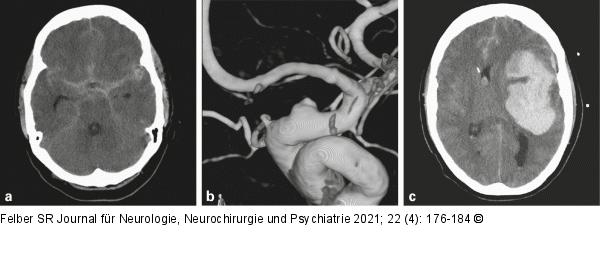

Abbildung 6a-c: Blister-Aneurysma Die 73-jährige Patientin stürzte zuhause, bei Eintreffen des Notarztes war die Patientin somnolent. Das CT (a) zeigte eine basale Subarachnoidalblutung und die Angiographie bestätigte ein kleines halbkugelförmiges Aneurysma (b). Innerhalb weniger Stunden, unmittelbar vor der geplanten Implantation eines flusskorrigierenden Stents, verstarb die Patientin an einer ausgeprägten Reblutung (c). |

Abbildung 6a-c: Blister-Aneurysma

Die 73-jährige Patientin stürzte zuhause, bei Eintreffen des Notarztes war die Patientin somnolent. Das CT (a) zeigte eine basale Subarachnoidalblutung und die Angiographie bestätigte ein kleines halbkugelförmiges Aneurysma (b). Innerhalb weniger Stunden, unmittelbar vor der geplanten Implantation eines flusskorrigierenden Stents, verstarb die Patientin an einer ausgeprägten Reblutung (c). |